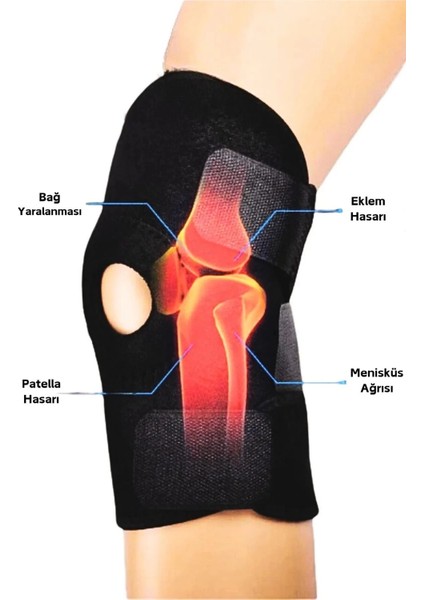

Diz Korsesi Çapraz Bağ Menisküs Ağrısı Için Dizlik Diz Bandajı Patella Dizlik

Diz Korsesi, çapraz bağ veya menisküs ağrısı yaşayanlar için ideal bir seçenektir. Patella Dizlik özelliği sayesinde dizinizi destekler ve korur, böylece spor yaparken veya günlük aktivitelerde rahatça kullanabilirsiniz. Bu Diz Bandajı, hafif ve esnek yapısıyla konforlu bir kullanım sunar.

- Çapraz bağ veya menisküs ağrısı olanlar için uygundur.

- Patella Dizlik özelliği sayesinde dizinizi destekler.